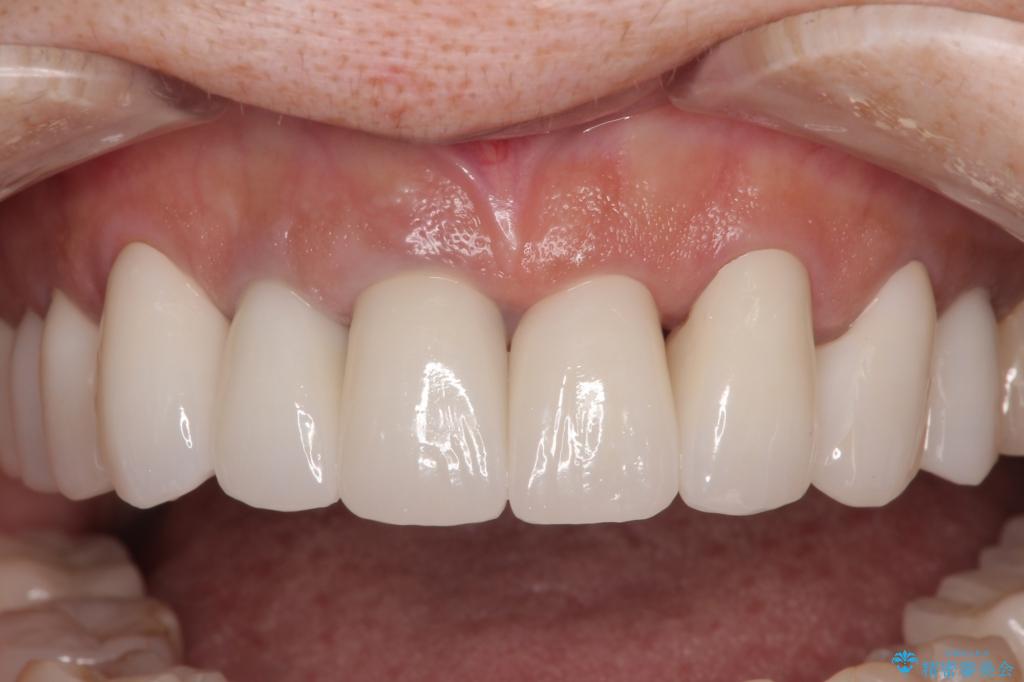

色調が統一されるだけでなく、歯肉ラインに見えていた茶色の境目も綺麗に改善されました。